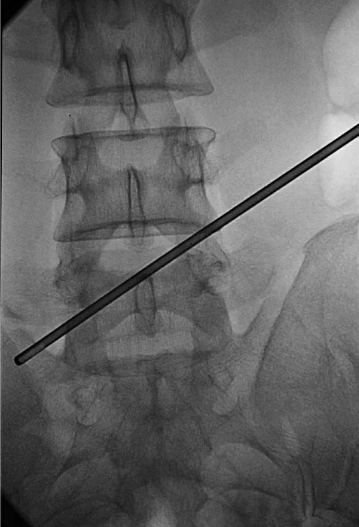

穿刺方向:线腰椎DR前后位上标出(图5)。

图5 腰椎DR前后位片穿刺方向线1.第一靶点;2.第二靶点;3.第三靶点

穿刺方向线:用抓钳前后位透视下确定(图9)。

图9 穿刺方向线:用抓钳前后位透视下确定

穿刺角度线:用抓钳侧位透视下确定(图10)。

图10 穿刺角度线:用抓钳侧位透视下确定

穿刺点:穿刺方向线与穿刺角度线的交点即为穿刺点,后正中线旁开13cm。